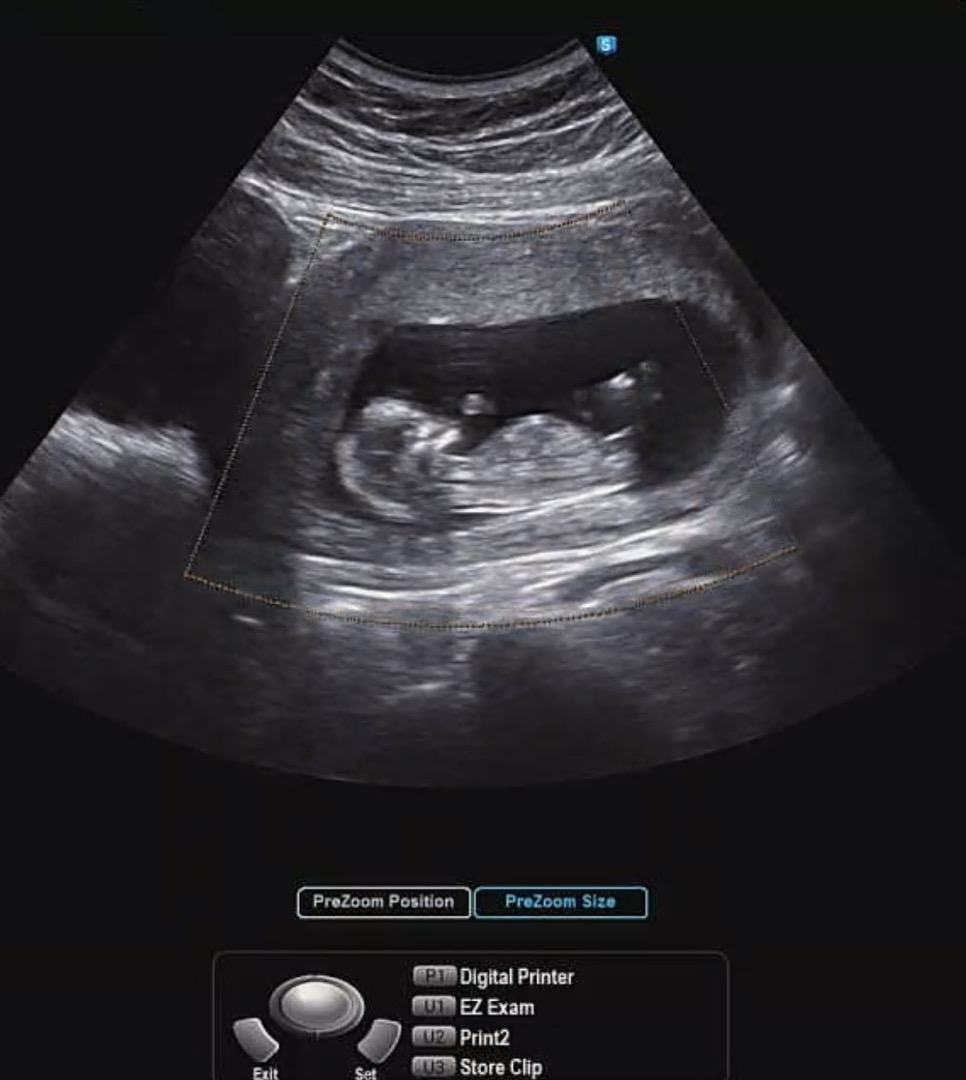

13주0일 각도법..!!

사진은 12주0일차 초음파입니다! 의견 부탁드립니다🥺